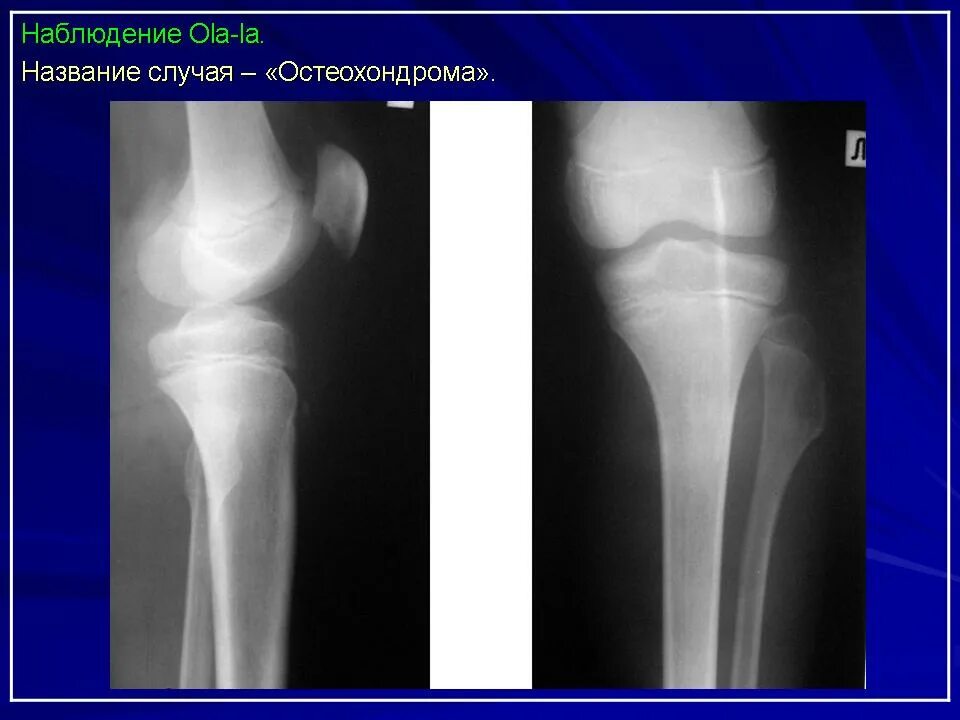

Экзостоз мкб 10